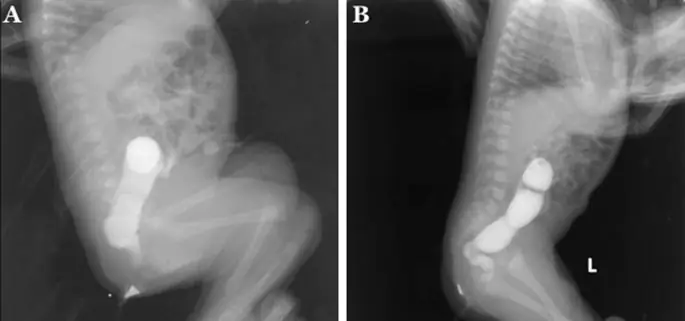

Для интраоперационных гистопатологических результатов мы определили ректальную группу, если длина аганглионоза была <7 см, и ректосигмоидную группу, если длина аганглионоза была ≥ 7 до ≤ 20 см (8) (рис. 1). Мы использовали гематоксилин и эозин (HE) в качестве окрашивания для интраоперационной гистопатологической оценки (11) (Дополнительный файл 1: Рис. S1).

Контрастная клизма выявляет переходную зону в: прямой кишке; и б ректосигмоидальный

Зону перехода при контрастной клизме определяли как место явного изменения калибра от недилатационной к расширенной ободочной кишке (10).